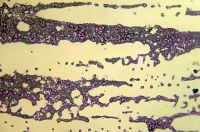

U pacientů po expozici malých a středně letálních dávkách ionizujícího záření se objevuje útlum krvetvorby 0,7 Gy a výše se objevuje na dávce závislý útlum krvetvorby v důsledku malé až nulové produkce krevních buněk vedoucí k pancytopénii. Míra poškozených kmenových buněk je úměrná dávce záření. Při dávce 1 Gy přežívá 37 % kmenových buněk (D0), při dávce 5 Gy 1 %.

Změny v počtu krevních elementů tvořících se v kostní dřeni se rozvíjí nejdříve po 24 hodinách od ozáření. Úbytek buněk souvisí s počtem buněk dané linie v kostní dřeni a mírou úhynu. Destruované buňky z kostní dřeně mizí a jsou nahrazovány částečně lipocyty. Pokles buněčnosti kostní dřeně je doprovázen dilatací sinusoidů, což má za následek časné krevní extravasáty, které jsou podobné skutečným hemorragiím. V případě leukocytů je změna výrazná, kdežto u erytrocytů se i u úplného zastavení produkce nových buněk v kostní dřeni projeví poklesem populace o 0,8 % denně. Navíc, expozice organizmu dávkám ionizujícího záření se manifestuje úbytkem nezralých forem krvetvorných buněk, kdežto formy diferencovanější bývají kvantitativně nedotčeny a dále vyzrávají a jsou i po ozáření uvolňovány do krevního oběhu. Změny v krevním obraze se tudíž manifestují až po dozrání zachovaných diferencovanějších stádií krevních elementů, v čase, kdy hypoplastická až aplastická kostní dřeň není schopna uvolnit do krevního oběhu další zralé buňky. Proto jednotlivé krevní elementy mizí z periférie v závislosti na délce života.

Útlum krvetvorby je značným klinickým problémem a projevuje se deficitem funkcí, které jednotlivé linie krevních buněk zastávají. Insuficience tvorby erytrocytů se projevuje anémií, pokles trombocytů má za následek zvýšenou tendenci k nekontrolovatelnému krvácení a úbytek granulocytů vede ke snížené rezistenci proti infekcím po minimálně 10 dnech od ozáření a příznaky trvají až do konce 6. -8. týdne po ozáření. Běžně se nástup klinických příznaků, jako jsou anémie, krvácení a snížená rezistence k infekcím, objevuje za 2 až 3 týdny po ozáření. Obecně je tíže útlumu hematologických ukazatelů dávkově závislá. Přítomnost jiných poranění urychluje čas nástupu a celkově prohlubuje maximum útlumu krvetvorby.

Kostní dřeň má značnou regenerační schopnost a i při dávkách přesahujících hodnotu 6 Gy přetrvávají ostrůvky schopné regenerace. Některá ložiska mo­hou být pouze abortivní, jiná právě postupně regenerují. V důsledku poškození chromozomů je možné pozorovat i četné abnormální mitózy a chromozómové aberace, z nichž některé mohou přetrvávat i řadu let. Jedná se především o výskyt chromatinových můstků, mikrojader, multioilárních mitóz a vznik obrovských bu­něk.